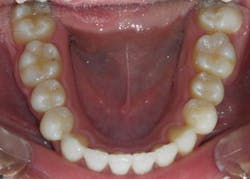

Figure 3: 36 mm is an appropriate width; the others display improper width and insufficient tongue space. Photos courtesy Dr. Ben Miraglia.

36 mm

30 mm

32 mm

25 mm

As the transverse measurement decreases, so does the “home” for the tongue. In Figure 3, you notice the narrowing of the arch and the increased vault of the palate in direct proportion to the decreasing width of the transverse (McNamara) measurement.